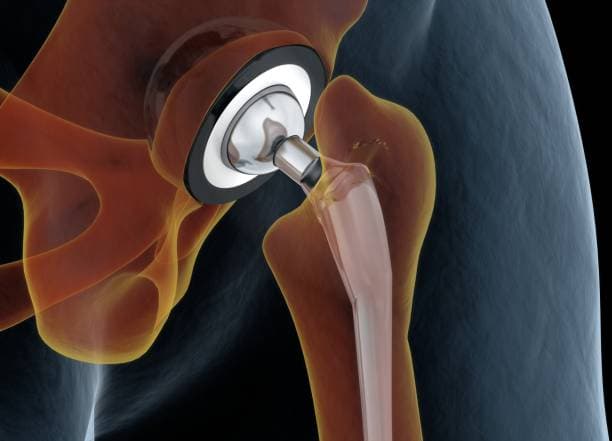

The surgical procedure involves making an incision over the hip, through which the surgeon accesses the joint. The damaged femoral head is removed and replaced with a metal or ceramic ball attached to a stem that fits into the femur. The acetabulum is also prepared by removing any damaged cartilage and bone, then resurfaced with a metal or plastic cup. These prosthetic components are designed to mimic the natural anatomy and movement of the hip joint, allowing for smooth articulation and reduced pain.

Implant Placement: The prepared bone surfaces are fitted with the prosthetic components. The femoral component, which includes a metal stem and a ball, is inserted into the femur. This can be cemented in place or designed to allow bone growth into the implant. The acetabular component, typically a metal shell with a plastic or ceramic liner, is placed into the prepared socket. These components are aligned to ensure proper joint movement and stability.

Total hip arthroplasty (THA) is the most common and widely performed hip replacement procedure. It involves replacing both the acetabulum (hip socket) and the femoral head (the ball) with prosthetic components made of metal, ceramic, or plastic. This procedure is typically recommended for patients with severe osteoarthritis, rheumatoid arthritis, or significant hip fractures that impair mobility and cause chronic pain. THA aims to relieve pain, improve joint function, and enhance the patient's quality of life. The prosthetic components are designed to mimic the natural movement of the hip joint, allowing for smooth and pain-free motion.